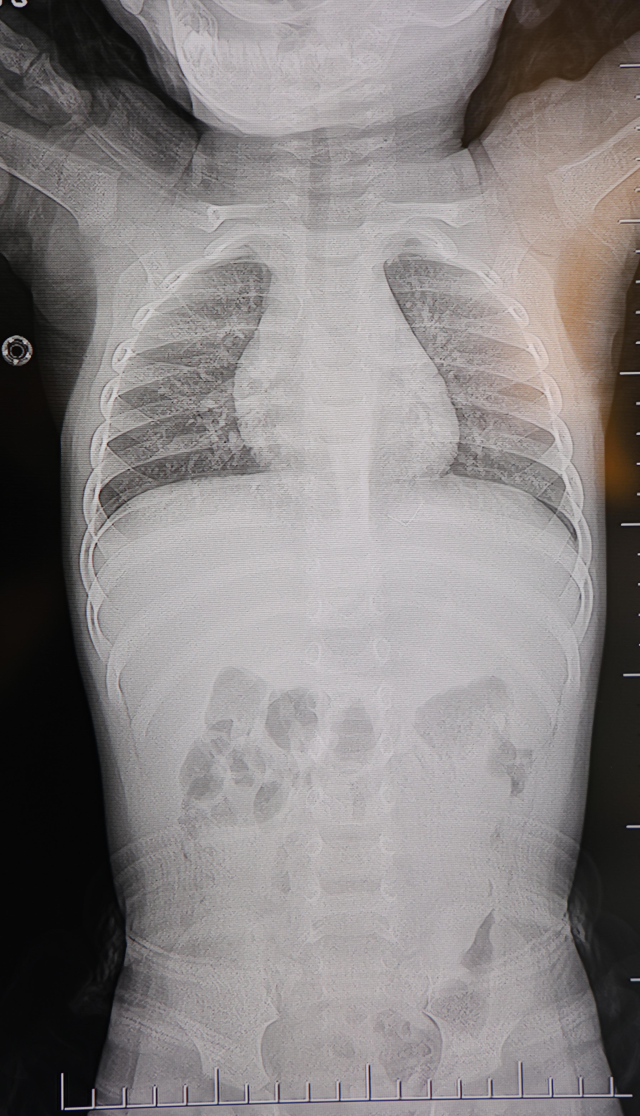

Kahramanmaraş'ta sırt üstü yatmak istemeyen ve yatırıldığında ağlayan ve huzursuzluk çıkaran 1 yaşındaki bebeğin sırtından akciğer zarına doğru ilerleyen 2 santimetrelik zımba teli çıkarıldı. Vakayla ilgili konuşan Prof. Dr. İdris Altun, "Cisim alınmasaydı enfeksiyon gelişebilir omurilik kanalında ciddi hasarlar oluşabilirdi" dedi.

Farklı ortopedi, çocuk cerrahisi ve beyin cerrahisi kliniklerine başvurusu yapılan bir yaşındaki bebeğin, sırt bölgesinde yabancı bir cisim olduğu ancak müdahalenin zor olduğu ve 8 yaşına kadar beklenmesi gerektiği bildirildi.

Ailenin son olarak başvurduğu hastanede yapılan tetkiklerde, yabancı cismin cilt altında, omurilik kanalına yakın bir bölgede olduğu ve akciğer zarına doğru ilerlediği belirlendi.

Hasta, genel anesteziye alınmadan, lokal anestezi ve sedasyon eşliğinde ameliyata alındı. Yapılan müdahalede yabancı cisim tamamen çıkarıldı. Çıkarılan cismin, ince zımba teline benzer metal bir tel olduğu ve yaklaşık 2 santimetre uzunluğunda bulunduğu tespit edildi. Hasta, aynı gün taburcu edildi.

Konuya ilişkin açıklama yapan Beyin ve Sinir Cerrahisi Uzmanı Prof. Dr. İdris Altun, "Sırtında yabancı bir cisim olduğu söylenmiş ancak çıkarılamayacağı ve 8 yaşına kadar beklenmesi gerektiği ifade edilmişti. Bize başvurduğunda yaptığımız tetkiklerde, cilt altında, omurilik kanalına çok yakın ve akciğer zarına doğru ilerleyen bir yabancı cisim tespit ettik. Hastamızı tamamen uyutmadan, lokal anestezi ve sedasyon eşliğinde müdahale ederek lezyonu tamamen çıkardık. Çıkardığımız cismin ince zımba teline benzer, yaklaşık 2 santimetre uzunluğunda metal bir tel olduğunu gördük. Bu yabancı cisim alınmasaydı, bölgede enfeksiyon gelişebilirdi. Enfeksiyon sonucu omurilik kanalında ciddi hasarlar oluşabilir, çocuk büyüdükçe cismin hareket etmesine bağlı olarak omurilikte zedelenmeler meydana gelebilirdi. Ayrıca yana doğru ilerleyerek akciğer zarına ve akciğere batma riski vardı. Bu da enfeksiyona ve ilerleyen süreçte tümörle karışabilecek tablolara neden olabilirdi. Şu an hastamız gayet sağlıklı. Gerekli kontrolleri yaptık ve aynı gün taburcu ettik" dedi.